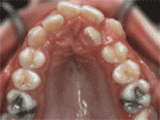

牙列拥挤主要常见牙齿过多,牙槽骨过窄,导致牙齿没有足够空间,一般根据检查结果,除了拔牙还有片切、扩弓、推磨牙远移等方法,不见得一定要拔牙。